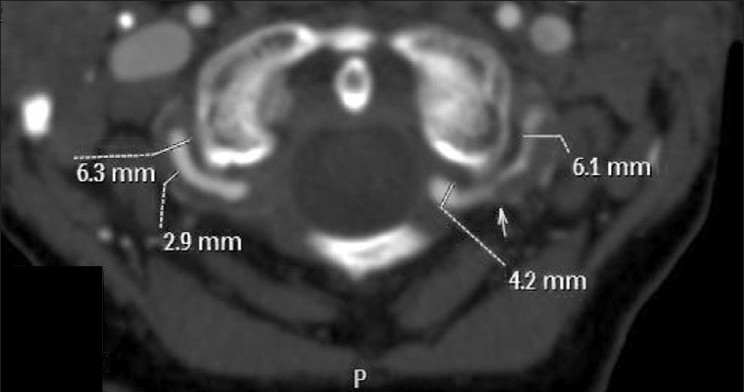

Figure 2.

This is an axial 2-mm MIP at the level of C1 of the same patient as in Figure 1. On the left, the total vessel diameter is 6.1 mm which reduces to the normal 4.2 mm diameter just at the dural margin. The shoulder where the dissection ends lies at the level of the arrow. On the right, the total vessel diameter is again increased, the wall of the vessel thickened at 2.9 mm and the vessel occludes at the level of the dura